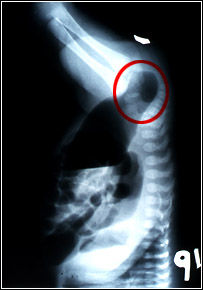

Defecto de desarrollo de la porción distal del intestino posterior, que queda cerrado, sin comunicación con la región perineal. La radiografia tomada con el recién nacido cabeza abajo, muestra la sombra rectal (círculo rojo), de fondo ciego, alejada de la marca radiopaca colocada en la región perineal.